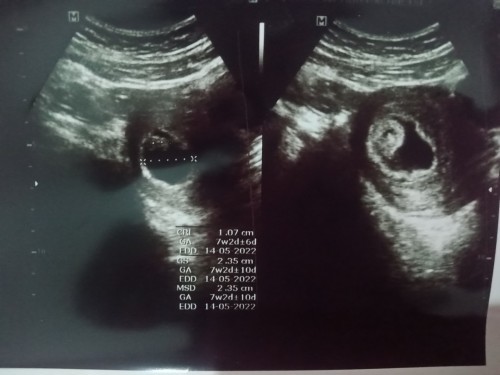

Bun, kemaren aku USG usia kandungan 8 Minggu. Hasil nya didalam kantung kehamilan ku seperti ada 2 janin. Dokter belum bisa memastikan itu janin atau apa. Diminta kontrol ulang 3 Minggu ke depan. Ada yg sama seperti yg kualami gak yaa Bun?#bantusharing #ingintahu #firstbaby #1stimemom #seriusnanya